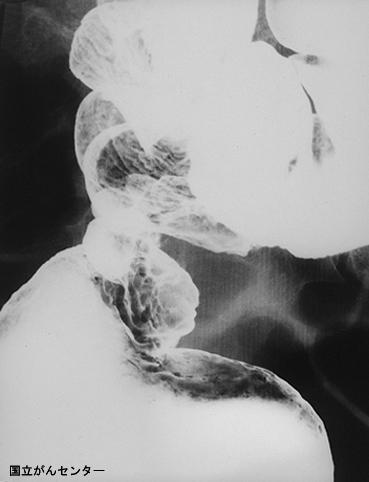

症例提示(所在地,施設名等): 東京都・ 国立がんセンター中央病院と九州がんセンターの共同作成

画像ID:5130

疾患(病理主体)の分類腫瘍様病変/子宮内膜症

部位(臓器別)大腸/直腸

検査方法X-P

病変の最大径(ミリ)40以上